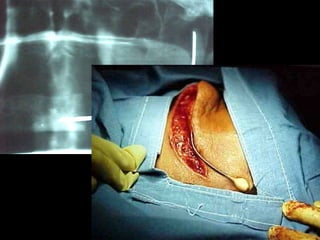

Zacapu 1970

Reimplante ortodóncico

Odontoma

1977

Receptor

Donante

Receptor momento de trasplante

Trasplante 3 meses de evolución